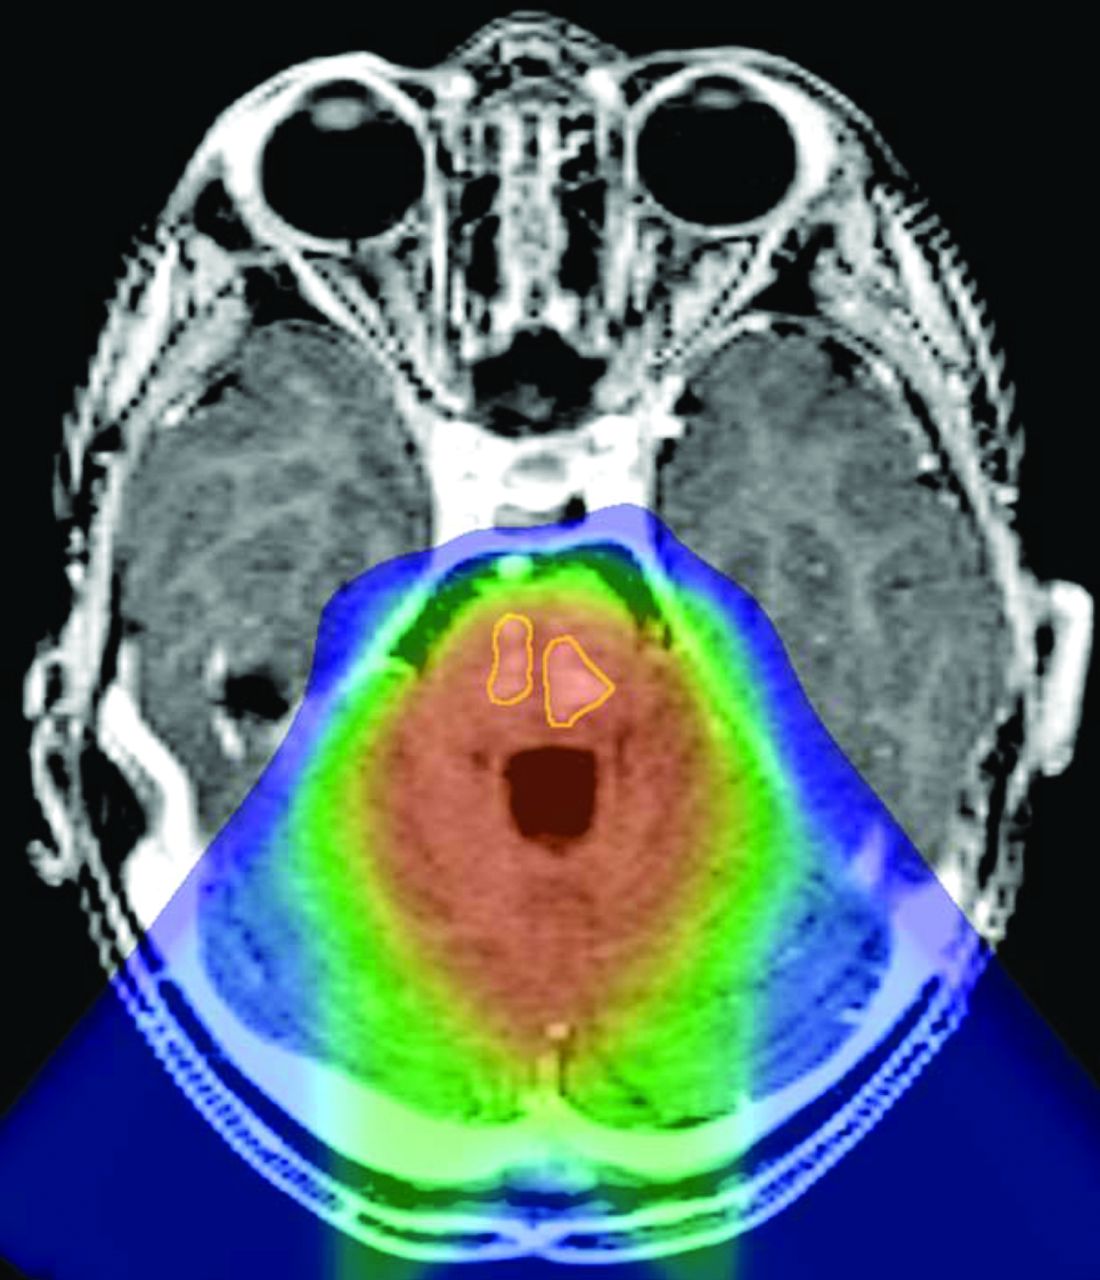

The areas of greatest imaging change were contoured on coregistered MR images and PT dose distributions for each patient. For 6 of the 8 patients, the areas of abnormal signal and enhancement approximately corresponded to areas of high dose (Fig 4). Among the 9 patients who did not show imaging changes after PT, 5 had supratentorial tumors (PNET = 4, ependymoma = 1) and 4 had posterior fossa tumors (ependymoma = 3, AT/RT = 1) in contrast to the 8 patients who developed radiation-associated changes, of which most (6/8) were posterior fossa tumors. The median age at diagnosis for the children who did not have changes after PT was 1.9 years, and the median age at the start of PT was 2.4 years, similar to the median age of diagnosis and start of PT of 1.8 and 2.5 years, respectively, in the patients with PT-related changes. One patient received only 50.4 CGE of therapy rather than the complete 54 CGE and died of progressive disease 8 months after completion of PT. Another patient, without evidence of radiation effect, died of progressive disease approximately 9.5 months after receiving 54 CGE.

Reformatted axial postgadolinium T1-weighted magnetization-prepared rapid acquisition of gradient echo image through the posterior fossa of patient 8, coregistered to the proton therapy treatment plan, demonstrates 2 areas of enhancement within the pons (outlined in yellow) located within the high-dose volume of irradiation (orange wash).